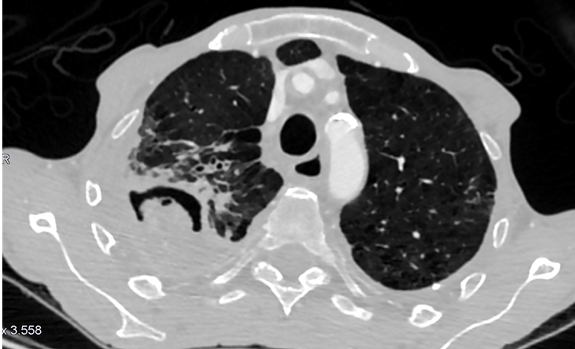

Es necesaria una prueba rápida, coste-beneficio rentable y que permita elegir un tratamiento empírico hasta obtener el diagnóstico de certeza: por ello elegimos la tomografía computarizada.